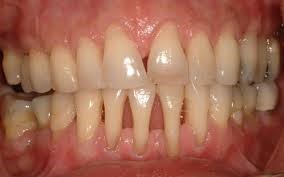

Крайне неприятным последствием пародонтоза является кровоточивость десен. Увеличение межзубных щелей и возникновение подвижности зубов. Оседание десен чревато оголением шеек и корней зубов и возникновению эффекта клиновидных зубов. Болезнь не только сопровождается болезненными ощущениями зубной эмали на термические и химические раздражители, но и существенно снижает самооценку больного. Болевые ощущения мешают полноценному питанию и общению, по утрам усиливается неприятный запах из ротовой полости.